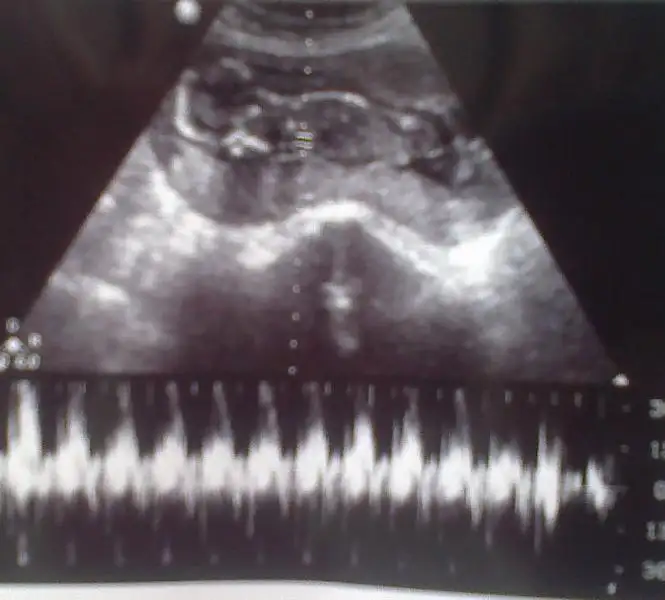

heycanım gitgide üst düzeye çıktı..kalbim sürekli çarpıyor.bebeğim 16 hafta 5 günlük oldu.yarın dr.a gidicem ama inanın gitmek istemiyorum.çok korkuyorum.ya bebeğime birşey olursa.ya omurgası açıksa diye.ben ilk bebeğim kaybettim.omurga açıklığından.2.ye sağlıklı bir kızım oldu.ama korkularım hiç geçmedi.bu 3.bebeğim olucak rabbim izin verirse inşallah.yarın güzel haberlerle dönmek çok istiyorum.ve hemen size buradan yazıcam.benim içinde dua edin neolur buna ihtıyacım var.hayırlısıyla bebeğimin sağlığı yerinde olsun......cinsiyet merakım ise yok oldu gitti.

canım benim için erkek dediysen neresine baktında anladın ben baktım baktım bişey anlamadım.gerçi dr.da erkeğe benziyor dedi.ama içimden bir kız geçiyor hayırlısı.yarın rabbimin izniyle herşey belli olucak ama benim başka korkularım var omurga açıklığı korkusu inşallah bebeğim sağlıklıdır.